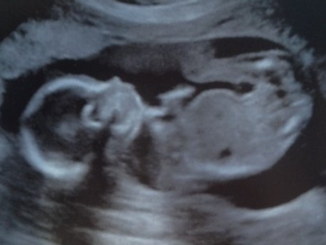

Two U.S. states have passed bills banning abortions from being performed after a heartbeat is detected during pregnancy. Lawmakers in Georgia and Tennessee are the two latest states to enact tough abortion laws following a […]